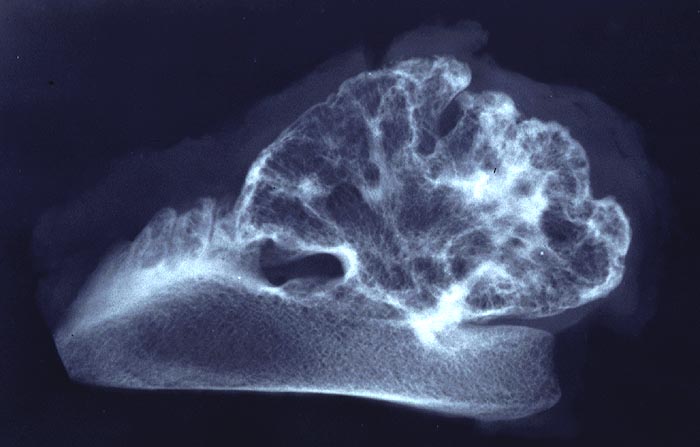

Im konventionellen Röntgenbild lassen sich gestielte und breitbasige Osteochondrome unterscheiden, wobei letztgenannte Formen immer vom Gelenk weggerichtet sind. Ein wichtiges Charakteristikum ist, dass die Spongiosa des Osteochondroms mit der Spongiosa des ortsständigen Knochens in Verbindung steht und die Läsion nicht einfach nur der Kompakta aufsitzt. Die Knorpelkappe ist im konventionellen Röntgenbild (> 5033) nur angedeutet erkennbar, kann aber im CT, MRI oder im Ultraschall dargestellt und ausgemessen werden. In der Mehrzahl der sporadischen aber v.a. der hereditären Osteochondrome lassen sich biallelische Inaktivierungen des EXT1 oder EXT2 Gens nachweisen, was die neoplastische Genese der Läsionen unterstreicht.

Osteochondrome sind breitbasig dem Knochen aufsitzende oder gestielte knöcherne Tumoren, die von einer 1-6mm dicken Kappe aus hyalinem Knorpel bedeckt werden. Zwischen Knorpel und Knochen liegt eine Zone enchondraler Ossifikation, die der normalen Wachstumsfuge ähnelt und den Ausgangspunkt für die Grössenzunahme des Tumors bei noch nicht abgeschlossenem Skelettwachstum darstellt. Der hyaline Knorpel wirkt etwas unorganisiert und ist bedeckt von einer dünnen Schicht Perichondrium.

• Kappenförmiges hyalines Knorpelgewebe ohne Zellatypien sitzt auf einem knöchernen Stiel. Die Knorpelkappe ist 2mm dick.